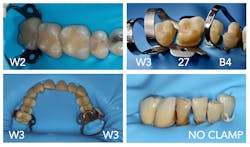

The common term “clamp” often does not properly explain the use of the rubber dam retainer. Most retainers are designed to hold the dam in place with the least amount of tissue harm possible (figure 9). Occasionally, more aggressive “clamps” may be employed when the soft tissue impedes access (like the 8A and 14A). However, the W3 is a useful clamp for routine molar isolations (figure 10).

When you need additional isolation on the tooth to be clamped, the 27 provides excellent distal access. The M17D clamp uses a third set of jaws that are positioned apically on the distal to retract for extensive caries while simultaneously allowing the handpiece access to the lesions. The PM18D performs the same function when premolars have a missing adjacent distal tooth (figures 11 and 12). Occasionally maxillary second or third molars, which are triangular, are best isolated with a W2 clamp turned 45 degrees toward the midline.

The key to patient comfort is to avoid aggressive clamps like the 8A and 14A whenever possible. When using flat-jawed clamps like the W series, additional local anesthetic is rarely necessary. A chart on rubber dam clamp use is helpful when deciding which retainer to use (figure 13).